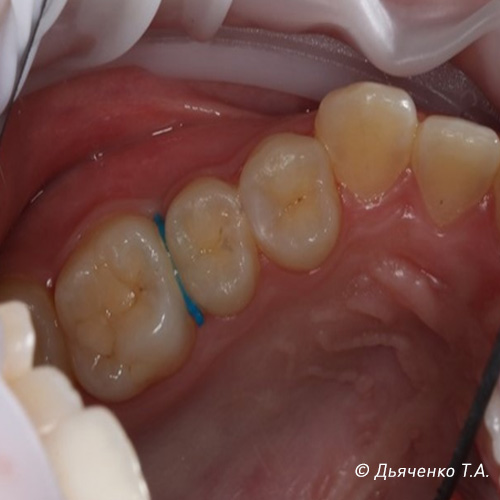

Пациенту ставиться межзубное сепарационное кольцо на 7 дней (рис. 9 и 10).

Через неделю кольцо убирается и контактный пункт раскрыт для лучшего обзора и лечения (рис. 11 и 12).